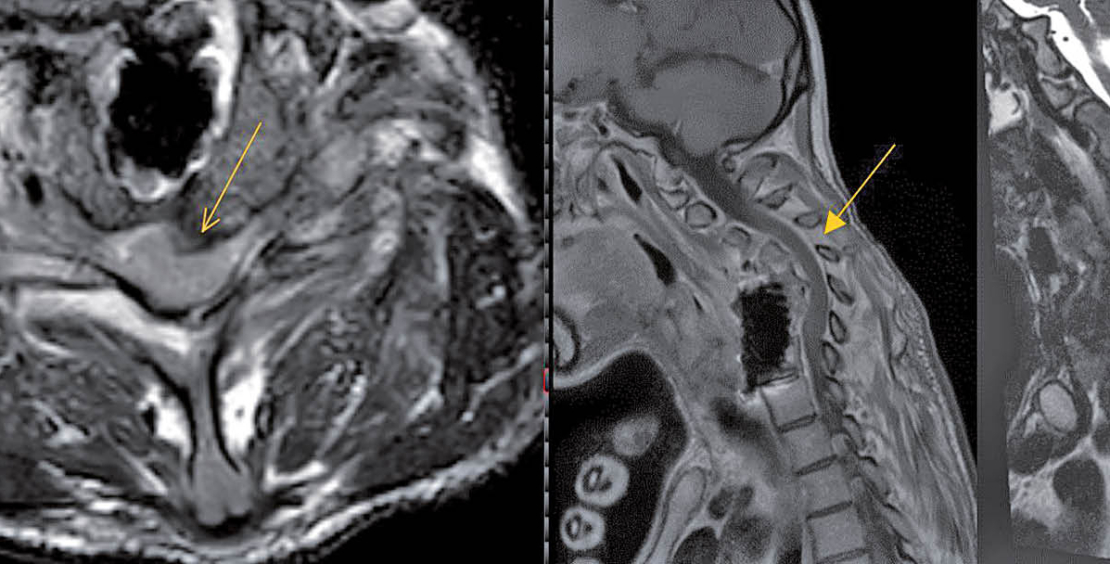

In der initial durchgeführten Computertomographie (CT) wurde eine Instabilität im Bereich der HWS diagnostiziert (Abb. 2). In der darauffolgenden Magnetresonanztomographie (MRI) zeigte sich eine leicht progrediente Anterolisthesis von HWK4 bei vorbestehender langstreckiger Kompression des Myelons mit Zeichen einer Myelopathie sowie diffusem Ödem. Eine Lockerung des Osteosynthesematerials konnte zwar nicht eindeutig nachgewiesen werden (Abb. 3), was eine solche naturgemäss nicht ausschliesst, jedoch wurde der Verdacht einer aus dem Implantat ausgehenden Spondylodiszitis gestellt (Abb. 4).